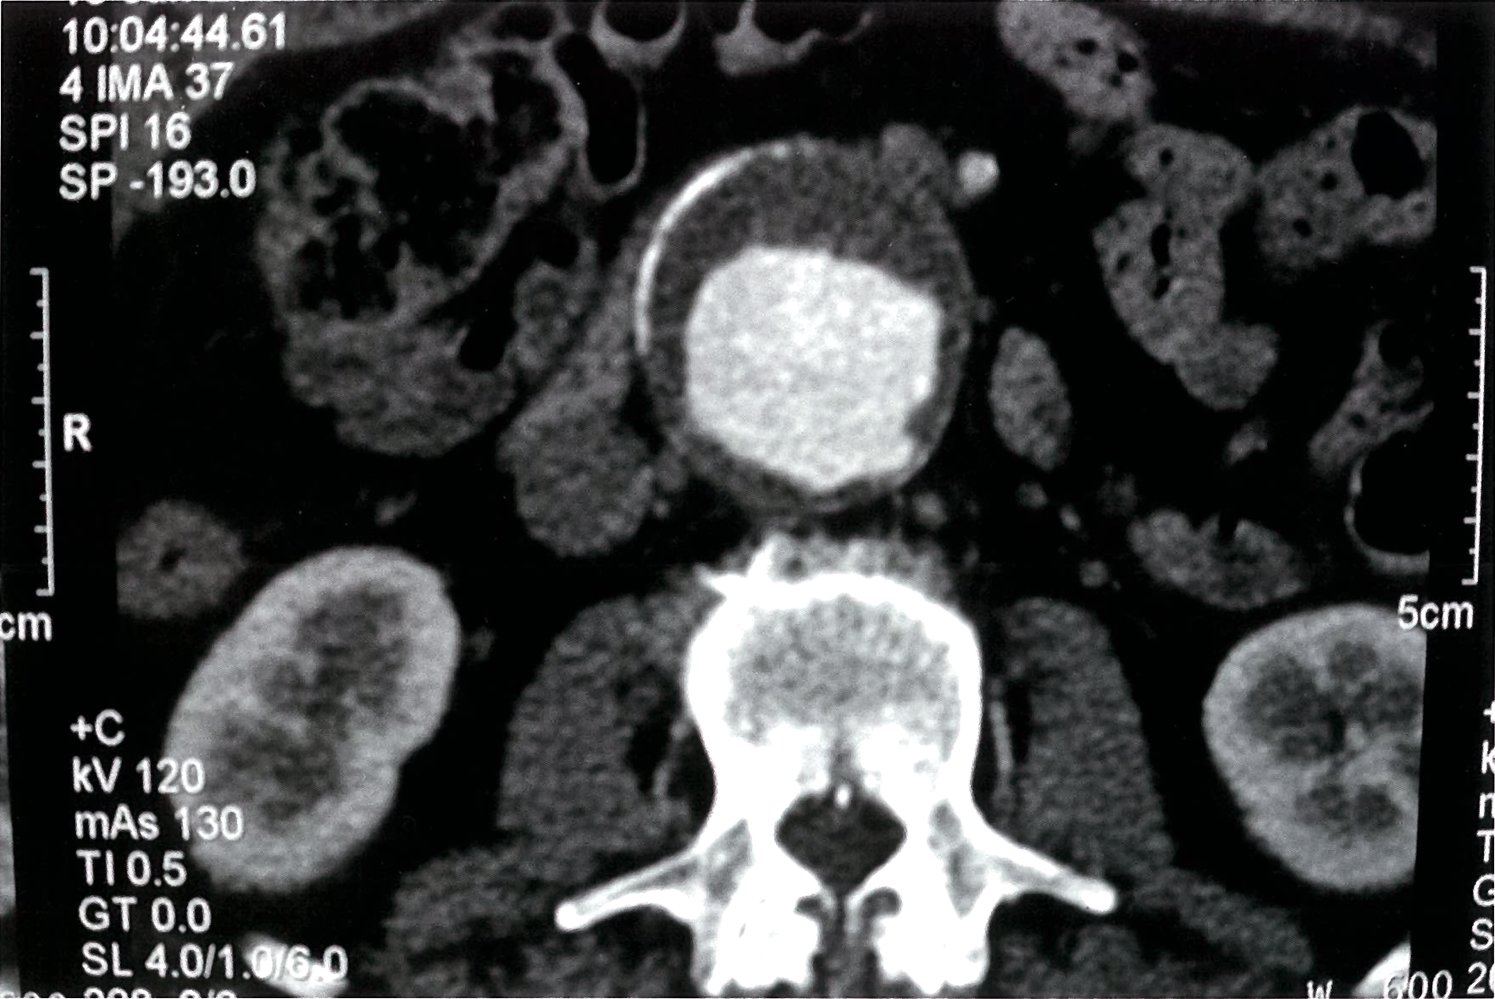

CT angiography abdomen and pelvis

See āRuptured AAAā for CT findings of acute aneurysmal rupture.

- Imaging modality of choice in symptomatic patients and for preintervention planning

- To help confirm the diagnosis when ultrasound is not possible in asymptomatic patients

- More detailed evaluation of the location, size, and extent of the aneurysm, involvement of branch vessels, and presence of thrombus or rupture

-

Supportive findings

- Dilatation of the aorta ā„ 3 cm and, possibly, branch vessels [1]

- Reduced distribution of vasa vasorum may be seen. [10]

- Thrombus may also be present (hypodense, nonenhancing).